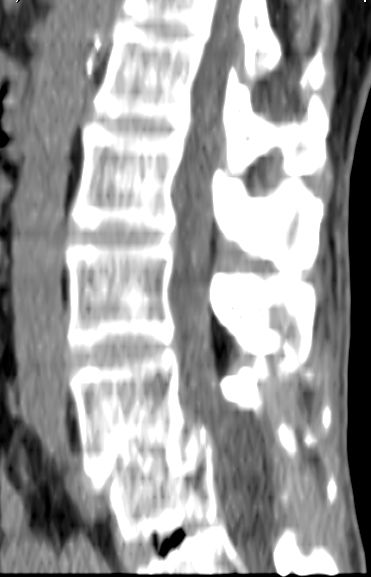

以下是引用余辉在2007-9-4 21:00:00的发言:[br]椎体棘突有点异常(像是被切割了),不知有否手术史,如椎体融合术等。单纯的退行性变可以出现椎间隙变窄,但同时一般会出现椎体上下缘的硬化增生,且椎体间完全融合的机率更小,本例椎体完全融合且椎体上下皮质缘破坏掉了,如果没有手术史,就应该考虑椎间盘炎性病变了,且椎体棘突及棘间韧带的变化也并不是不支持这个,多数小关节也融合了,且其形态也容易让人联想到如强脊炎及类风关等病变。[br][br][本贴已被 余辉 于 2007-9-4 21:03:55 修改过]

以下是引用chry3在2007-9-4 20:42:00的发言:[br]椎间盘病史?是什么样的病史,无双下肢放射痛,那就不是椎间盘突出了。是感染、什么性质的?[br]从图象看椎间隙消失,椎间盘组织未见,锥体滑脱是因为椎间盘溶解造成的[br]l4、5椎体骨质结构未见异常,l5上缘是l4的长期压迫所致[br]还是考虑椎间盘感染,结核。[br]